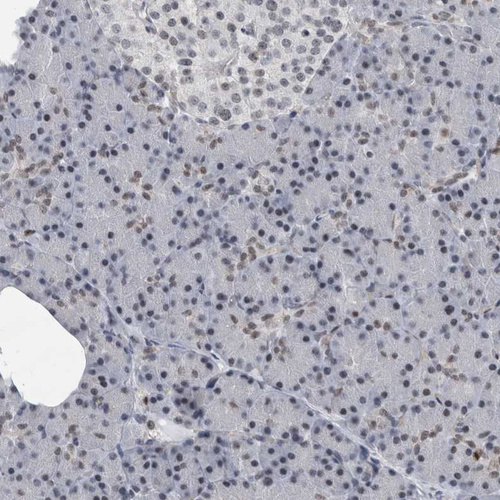

Immunohistochemical staining of human Fallopian tube shows moderate nuclear positivity in glandular cells.